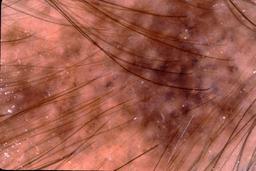

{

"age_approx": 55,

"anatom_site_general": "lower extremity",

"concomitant_biopsy": true,

"dermoscopic_type": "contact non-polarized",

"diagnosis_1": "Malignant",

"diagnosis_2": "Malignant adnexal epithelial proliferations - Follicular",

"diagnosis_3": "Basal cell carcinoma",

"diagnosis_confirm_type": "histopathology",

"image_type": "dermoscopic",

"lesion_id": "IL_9320857",

"melanocytic": false,

"patient_id": "IP_5255747",

"sex": "female"